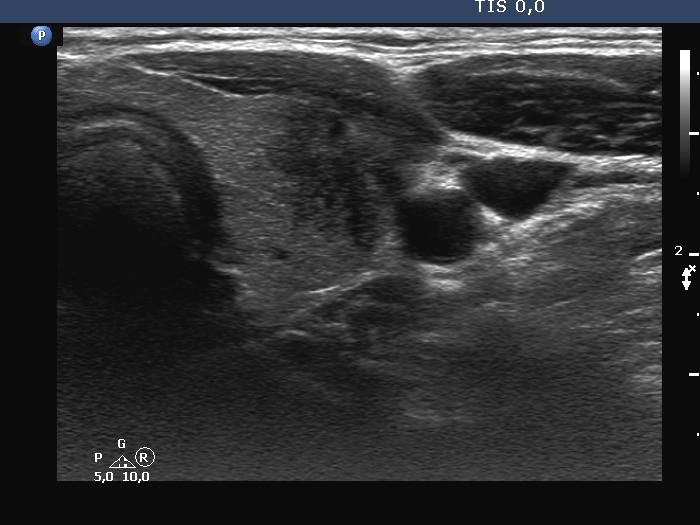

Second examination a year later (second row of images):

Clinical presentation: The complaints of the patients has fully ceased several days after the former visit and had not recur.

Palpation: no abnormality.

Laboratory tests: TSH 0.39 mIU/L on daily 50 microgram levothyroxine.

Ultrasonography. The thyroid has significantly decreased in size. The echogenicity became normal. The left lobe has already had discrete hypoechoic lesions but the size of them was much smaller compared with the previous visit.

Suggestion: to stop replacement therapy. TSH in 6 months, ultrasound in 3 years.